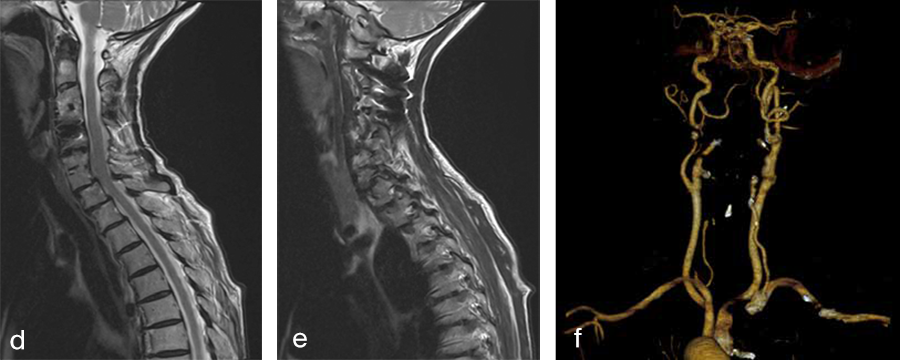

Fig 2a–f Preoperative imaging showing: C2-C4 posterior instrumentation and fusion, anterior fusion after anterior cervical decompression and fusion (ACDF) C3/4 and C6/7, status after total disc replacement of C4/5 with heterotopic ossifications, nonunion C5/6 after ACDF C5/6, spondylolisthesis C7/Th1 with neuroforaminal stenosis on both sides and a normal cervical angiogram (cave: artefacts).